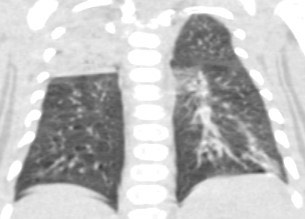

1940. Пациенту 3 месяца с диагнозом «медуллобластома», состояние после оперативного вмешательства и полихимиотерапии, выполнена компьютерная томография, рентгенологическая картина соответствует